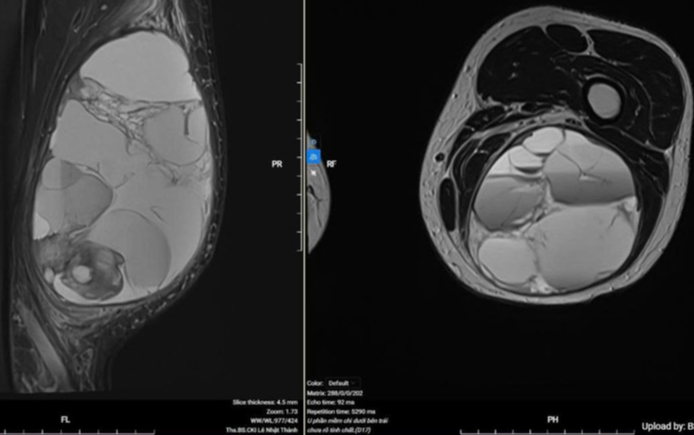

Kết quả chụp MRI cho thấy tổn thương rộng ở mặt sau đùi trái bệnh nhân. Ảnh: BVCC

Kết quả chụp CT toàn thân cho thấy ung thư chưa di căn về mặt đại thể. Hình ảnh MRI tại chỗ ghi nhận khối u rất lớn, chèn ép và xô đẩy các cấu trúc giải phẫu lân cận.